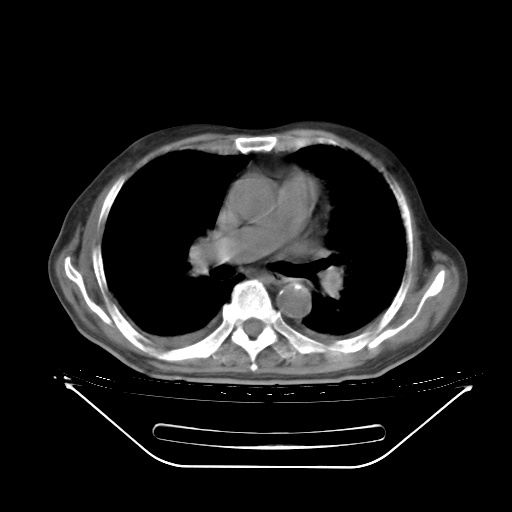

5月9日肺部CT(在4月27日齐鲁医院肺部CT描述部分肺组织磨玻璃样改变,12天后肺组织广泛磨玻璃样改变)

2009年5月9日肺部CT

大致读了系列胸部CT:纵隔窗无明显异常,肺窗:从4、27至今:主要是双肺中下野外带可见毛玻璃样改变,目前处于急性肺泡炎阶段,至于原因考虑1、结替组织或胶原血管性疾病所致?2、恶性疾病如恶组在肺部所致的表现或细支气管肺泡癌?3、药物或其它原因如肺蛋白沉着症所致肺泡炎目前不太可能?总之,明天就去请我院的呼吸科、感染科、血液科和临免专家会诊哈。